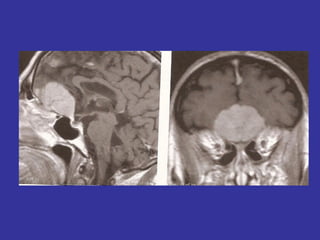

Lesões quiasmáticas (tumores de hipófise)=> hemianopsias bitemporais

(comprometimento das fibras nasais de cada retina)